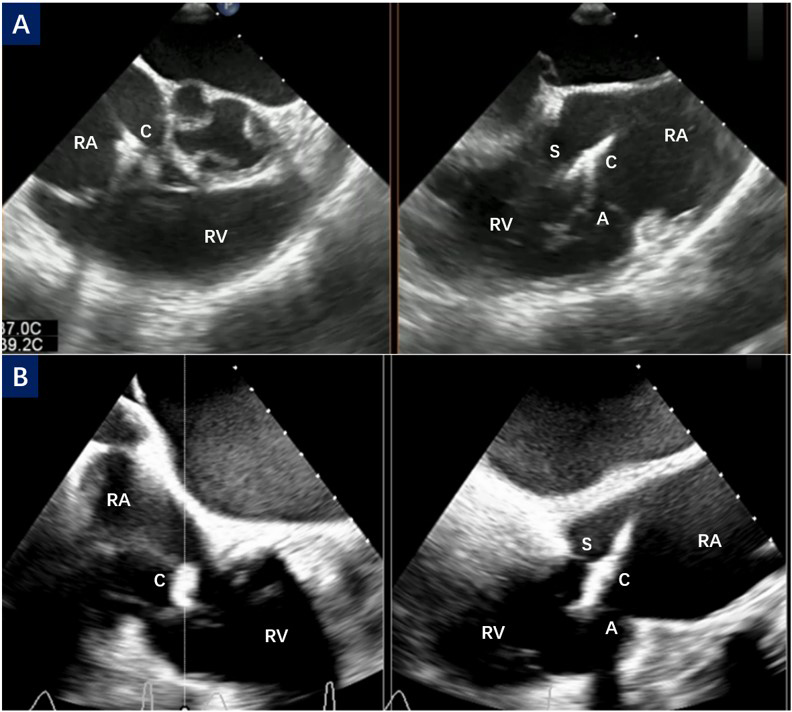

Fig. 1.

CDS orientation and septal hugger. (A) The right ventricular inflow/outflow tract view and biplane view of TEE show the orientation process of CDS toward the tricuspid valve. (B) The CDS points obliquely to the tricuspid valve, also known as the septal hugger. C, clip; S, septal leaflet; A, anterior leaflet; RA, right atrium; RV, right ventricular; TEE, transesophageal echocardiography; CDS, Clip Delivery System.